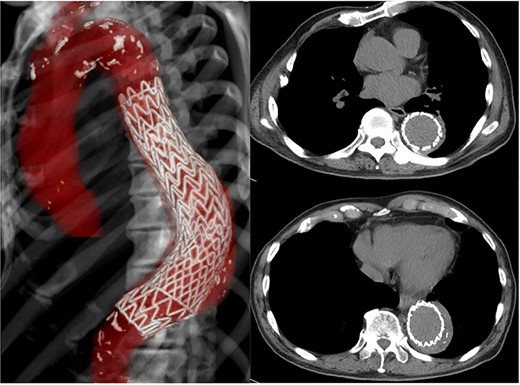

The patient had a fever (38°C) for 4 days after hospitalization, but his temperature dropped to 37°C afterward. His inflammatory reaction gradually improved, but CT angiography showed a descending aortic aneurysm, measuring 70 × 70 mm (Fig. 2). It extended 20 mm in only 2 weeks.

Preoperative CT shows acute expansion of the aneurysm to 70 mm in diameter.